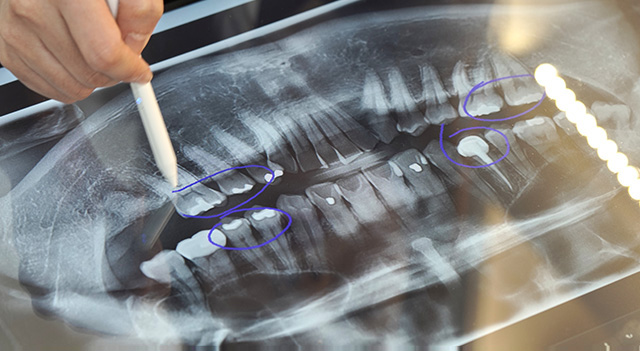

3D 데이터로 철저한 수술 계획 수립 후 초정밀 식립

치조골의 구조와 신경 위치를 확인하여 치료 계획을 수립하고,

모의 수술 및 수술용 가이드 제작을 통해

보다 빠르고 정확한 임플란트 식립이 진행됩니다.